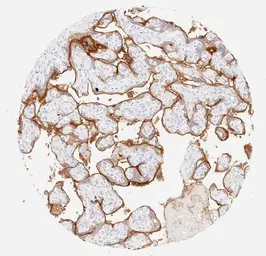

Anti-PD-L1 antibody [H302] HistoMAX&trade; used in IHC (Paraffin sections) (IHC-P). GTX639925

GTX639925 IHC-P Image

IHC-P analysis of human placenta (mature) tissue using GTX639925 PD-L1 antibody [H302] HistoMAX™.

Strong PD-L1 staining of the external membrane of the syncytiotrophoblast.